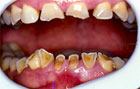

La angulación de los cóndilos en el plano axial (12), el insuficiente desarrollo de los cóndilos (Hipoplasia) (13, 14), son factores que favorecen la aparición de patología y más aun si se añaden sobrecargas funcionales. Un cóndilo hipoplásico (Fig. 1) nos obligará a proteger más las articulaciones durante la realización de las higienes dentales, para no sobrecargarlas y favorecer así la aparición de patología.

Fig. 1 Hipoplasia Condilar